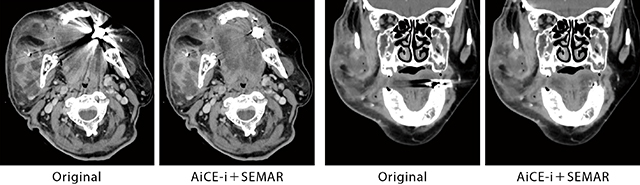

図3 右咬筋膿瘍、下顎骨右筋突起裏面膿瘍の治療効果判定

SEMARとAiCE-iの併用により、義歯周辺の金属アーチファクトが劇的に低減するだけでなく、効果的にノイズ低減が可能となり、周囲組織の辺縁を明瞭に観察可能であった。